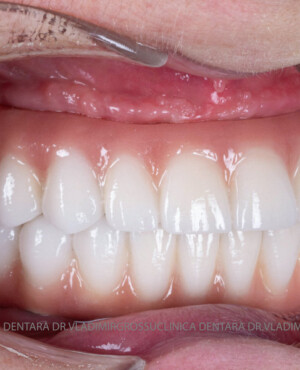

Caz 2

- Posibilitatea realizării unei proteze cu 12-14 dinți, oferind un aspect estetic natural și funcționalitate optimă.